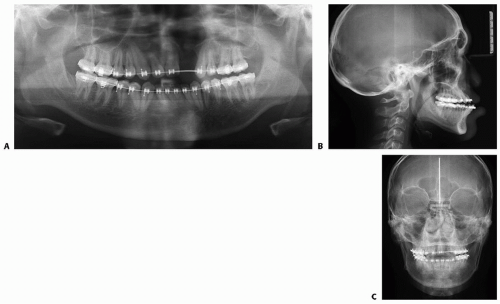

Traditionally, posteroanterior and lateral cephalograms as well as a panoramic x-ray are obtained (FIG 6).